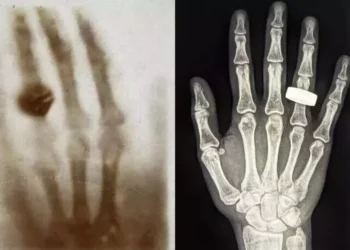

Etiqueta: Una mano con un anillo